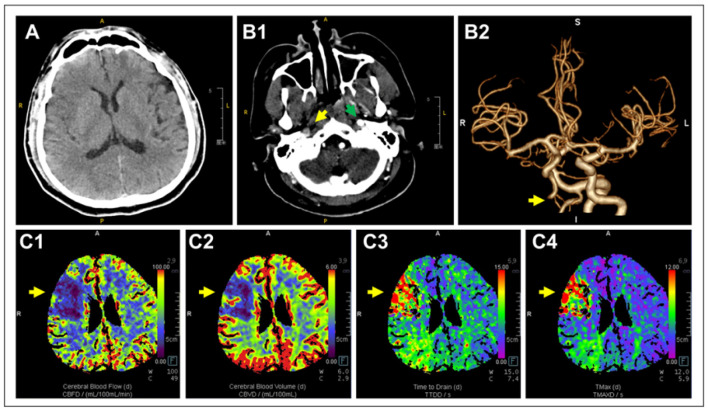

主动脉夹层(Aortic dissection, AD)是一种危及生命的心血管急症,其特征是由于内膜撕裂导致主动脉内层和中间层分离。根据撕裂的位置和程度将其分为斯坦福A型或B型。症状各不相同,但通常包括胸部、背部或腹部的剧烈疼痛,并伴有非典型症状,如休克、心力衰竭或晕厥。终末器官缺血,包括中风和肢体坏死,可能发生。及时诊断和干预对生存至关重要。在这里,我们报告了一位31岁的男性患者,他表现出急性神经系统症状,最初怀疑有中风,但最终通过计算机断层扫描(CT)血管造影诊断为斯坦福a型AD。本病例强调了在神经系统症状患者鉴别诊断中考虑AD的重要性,以获得准确和及时的治疗。

Aortic dissection (AD), a life-threatening cardiovascular emergency, is characterized by the separation of the aorta's inner and middle layers due to a tear in the intima. It is classified as Stanford type A or B based on the tear's location and extent. Symptoms vary but commonly include severe pain in the chest, back, or abdomen, along with atypical presentations such as shock, heart failure, or syncope. End-organ ischemia, including stroke and limb necrosis, may occur. Timely diagnosis and intervention are crucial for survival. Here, we report a 31-year-old male patient who presented with acute neurological symptoms, initially suspected of having a stroke, but was ultimately diagnosed with Stanford type A AD upon computed tomography (CT) angiography. This case underscores the importance of considering AD in the differential diagnosis of patients with neurological symptoms for accurate and prompt management.